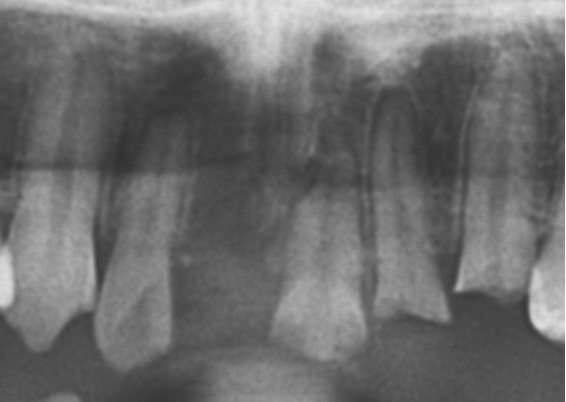

下の写真は交通事故により折れた歯と抜けた歯です。